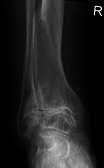

Diagnosis is made with reasonable certainty based on history and clinical examination.[42][43] X-rays may confirm the diagnosis. The typical changes seen on X-ray include: joint space narrowing, subchondral sclerosis (increased bone formation around the joint), subchondral cyst formation, and osteophytes.[44] Plain films may not correlate with the findings on physical examination or with the degree of pain.[45] Usually other imaging techniques are not necessary to clinically diagnose OA.

Severe osteoarthritis and osteopenia of the carpal joint and 1st carpometacarpel joint.